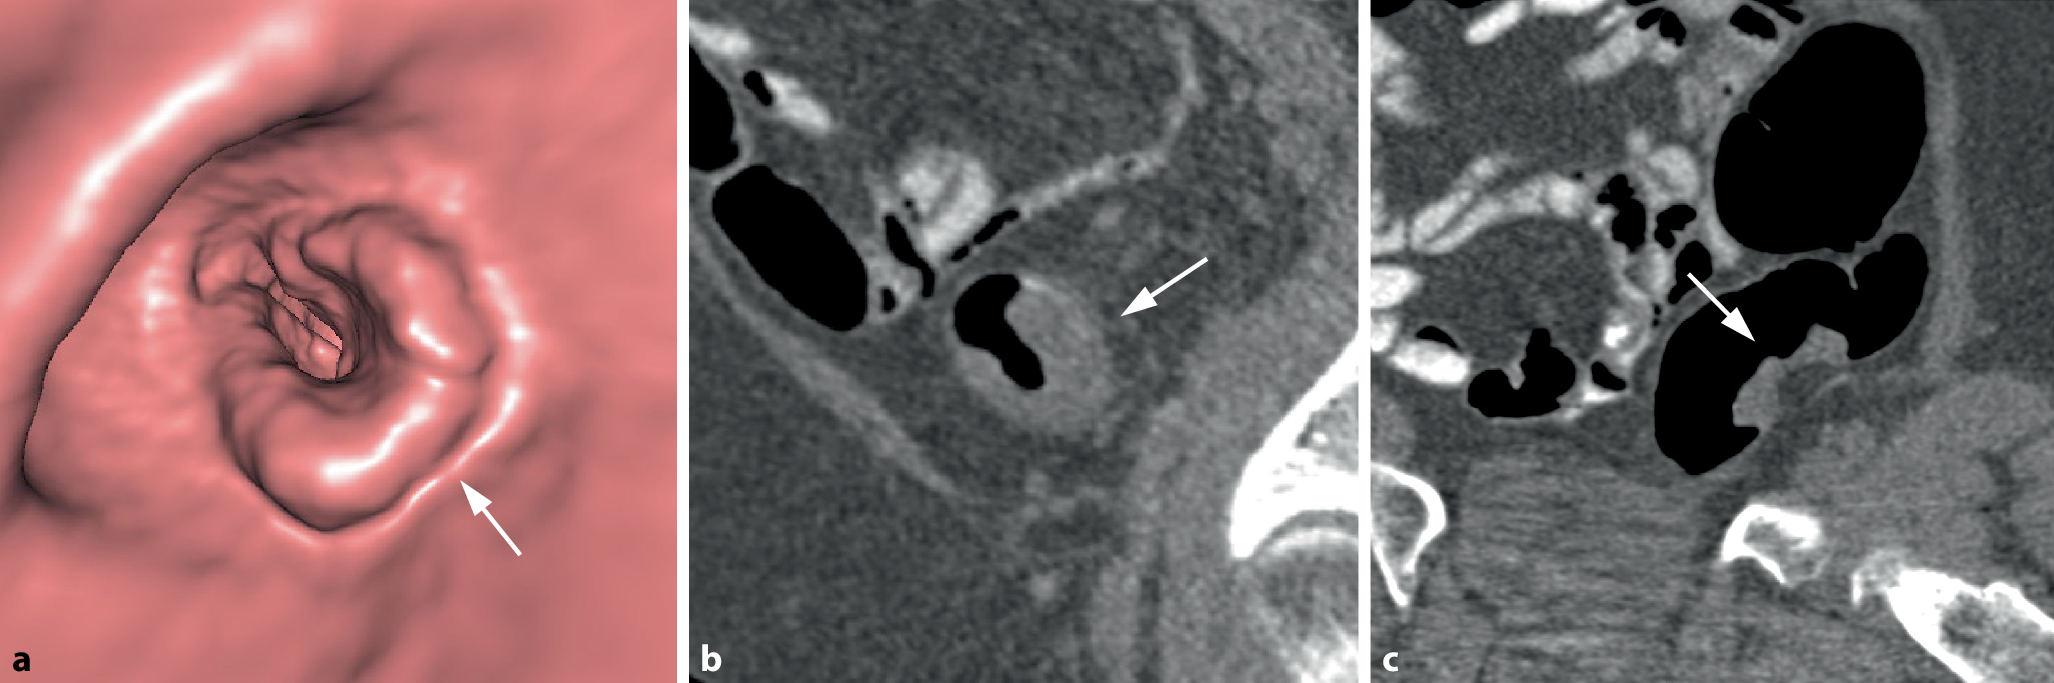

Bei semizirkulären Tumoren nimmt die tumoröse Wandverdickung nur einen unterschiedlich großen Anteil der Zirkumferenz eines Darmsegments ein (Abb. 3). Bei kleineren Tumoren kann sich dabei in der 3D-Darstellung ein Aspekt ergeben, der an einen Pferdesattel erinnert (Abb. 4).

Abb. 3

Semizirkuläres Karzinom im Colon sigmoideum. a Die endoluminale 3D-Ansicht und das korrespondierende parasagittale (b) und parakoronare 2D-Bild (c) zeigen die tumoröse Wandverbreiterung mit Schulterformation, die nur einen Teil der Dickdarmzirkumferenz betrifft (Pfeil). c Das parakoronare 2D-Bild zeigt die kurzstreckige Tumorlängsausdehnung und die homogene, weichteildichte Struktur (Pfeil)

Abb. 4

Sattelförmiges Karzinom im mittleren Rektum. a Die endoluminale 3D-Ansicht zeigt eine kleine sattelförmige Läsion im mittleren Rektum (Pfeil). b Das axiale 2D-Bild zeigt eine kurzstreckige semizirkuläre Wandverbreiterung mit Schulterbildung und weichteildichter Struktur (Pfeil)

Bild vergrößern